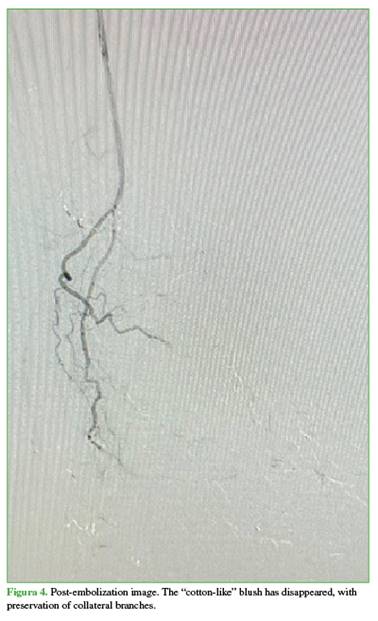

The patient reported marked symptomatic relief following embolization (Figure 3).

The technique consists of superselective embolization of genicular arterial branches supplying areas of synovial neoangiogenesis, seeking a controlled reduction—though not complete occlusion—of flow to the pathological vessels, in order to decrease inflammation and pain while minimizing the risk of ischemia in adjacent tissues (Figure 4).13